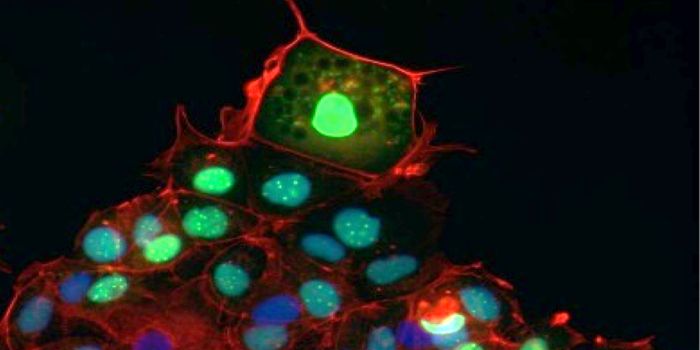

DEC 10, 2015ImmunologySuperior technology brings us novel images of cancer cells and lymphocytes this week, and now scientists can learn more ...